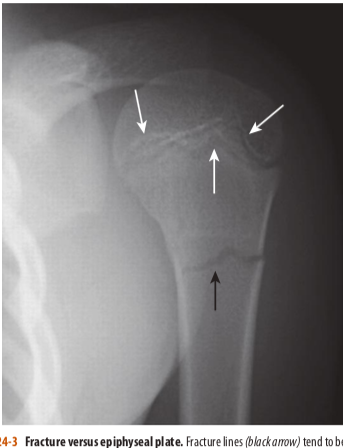

Fracture versus epiphyseal plate.

Fracture lines (blackarrow)tend to be straighter in their course and more acute in their angulation than any naturally occurring lines, such as the epiphyseal plates in the proximal humerus (white arrows). Because the top of the metaphysis has irregular hills and valleys, the epiphyseal plate has an undulating course that will allow you to see it in tangent, both on the anterior and posterior margins of the humeral head. This gives the mistaken appearance that there is more than one epiphyseal plate.